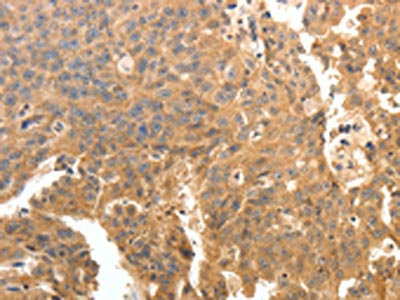

The image on the left is immunohistochemistry of paraffin-embedded Human ovarian cancer tissue using CSB-PA246334(PTPRE Antibody) at dilution 1/10, on the right is treated with fusion protein. (Original magnification: ×200)

The image on the left is immunohistochemistry of paraffin-embedded Human cervical cancer tissue using CSB-PA246334(PTPRE Antibody) at dilution 1/10, on the right is treated with fusion protein. (Original magnification: ×200)